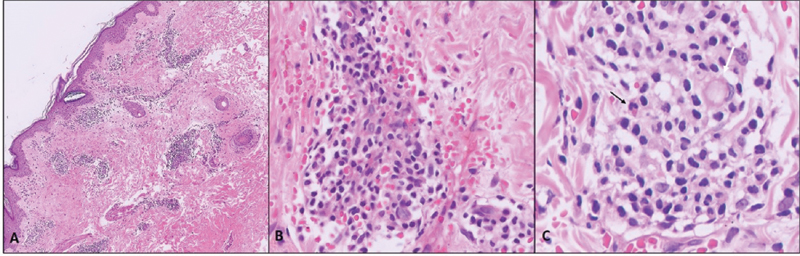

A dermatology opinion was taken, and skin biopsy was done from the left leg, in which perivascular mononuclear inflammation in superficial and deep dermis was found, with red blood cell extravasation and neutrophilic infiltration in the vessel walls. A diagnosis of small vessel vasculitis secondary to tamoxifen was then done ([Fig. 2]). Tamoxifen was stopped, and she was given letrozole 2.5 mg OD along with the ovarian suppression. She was given antihistamines (cetirizine) and fusidic acid for a week, after which she was prescribed halobetasol 0.05%-for topical application, along with vitamin C and moisturizing lotions, for a period of 2weeks. The symptoms resolved completely within 1 month and the patient was continued on letrozole with leuprolide.

| Figure 2: (A) Skin biopsy micorphotographs: (A) Dense perivascular inflammation around upper and mid-dermal vessels (hematoxylin and eosin [H&E] x100); (B) inflammatory infiltrate of lymphocytes, neutrophils, eosinophils, and plasma cells. Red blood cell extravasation with hemosiderin staining (golden brown). Vascular outlines not clear (H&E, x400); (C) vessel wall fibrinoid necrosis (white arrow) and eosinophil (black arrow).